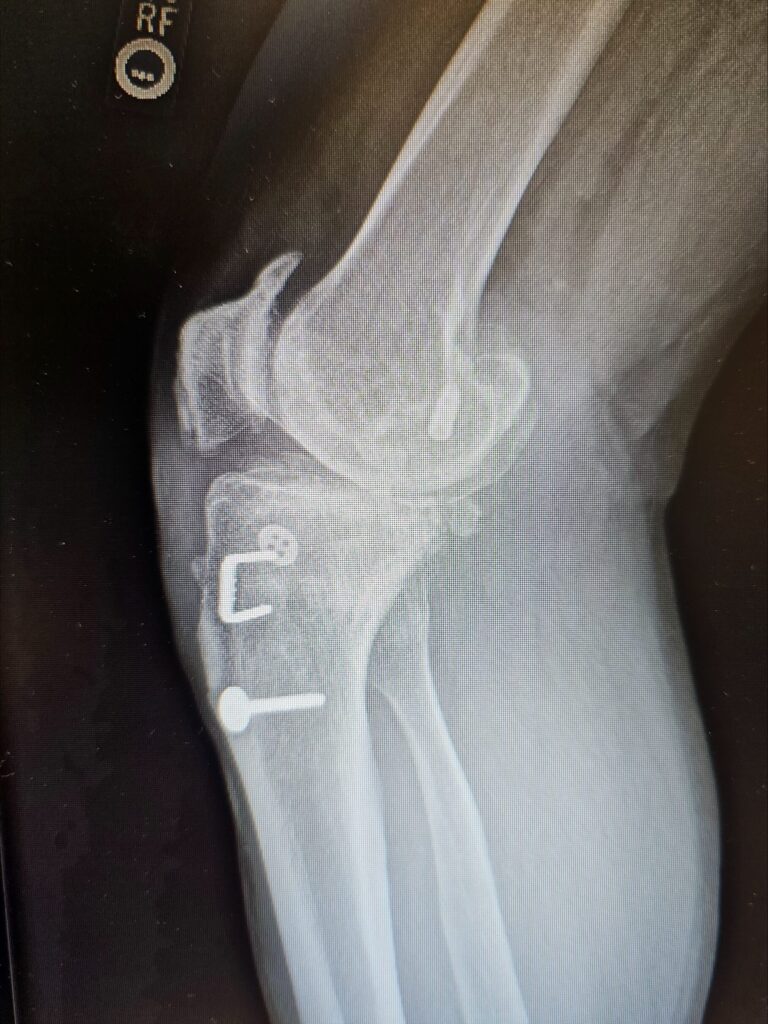

Last week marked a significant milestone in orthopedic surgery as Dr. Jared T. Lee, Medical Director and orthopedic surgeon at The Steadman Clinic in Aspen, Colorado, successfully performed the 5th ever customized press-fit total knee replacement in the United States — a monumental achievement that reflects his commitment to precision, innovation, and patient-centered care.

Traditional total knee replacements typically use standard implants fixed to bone with medical cement. In contrast, press-fit implants are designed to achieve stability through bone ingrowth — allowing the patient’s own bone to integrate with the implant surface over time rather than relying on cement fixation.

A customized press-fit knee goes even further: using advanced imaging (such as MRI or CT scans) taken before surgery, the implant is individually designed to match the exact anatomy of the patient’s knee joint. This tailored fit can improve alignment, preserve more bone, and maximize contact with the surrounding bone structure.